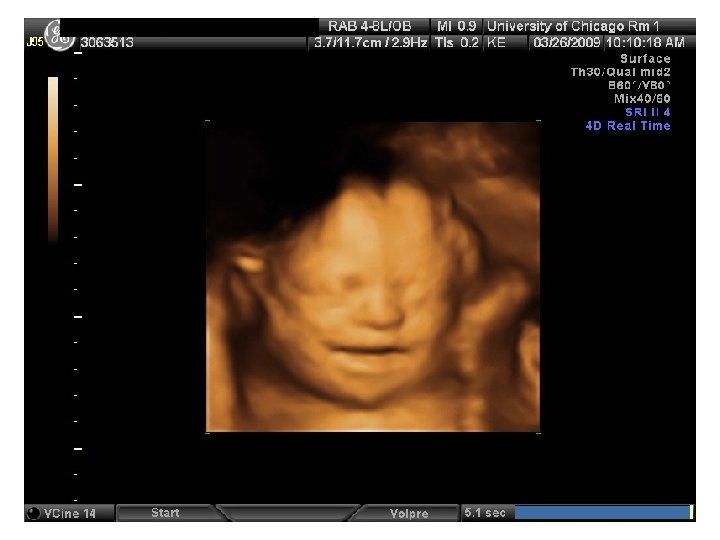

QUIZ What is Your Diagnosis? Case: Patient J. F. 30 years old, at 32 week gestation. Presented with the following pictures.

Answer: a) Trisomy 21 b) Non-immune Hydops c) Paravo virus Infection